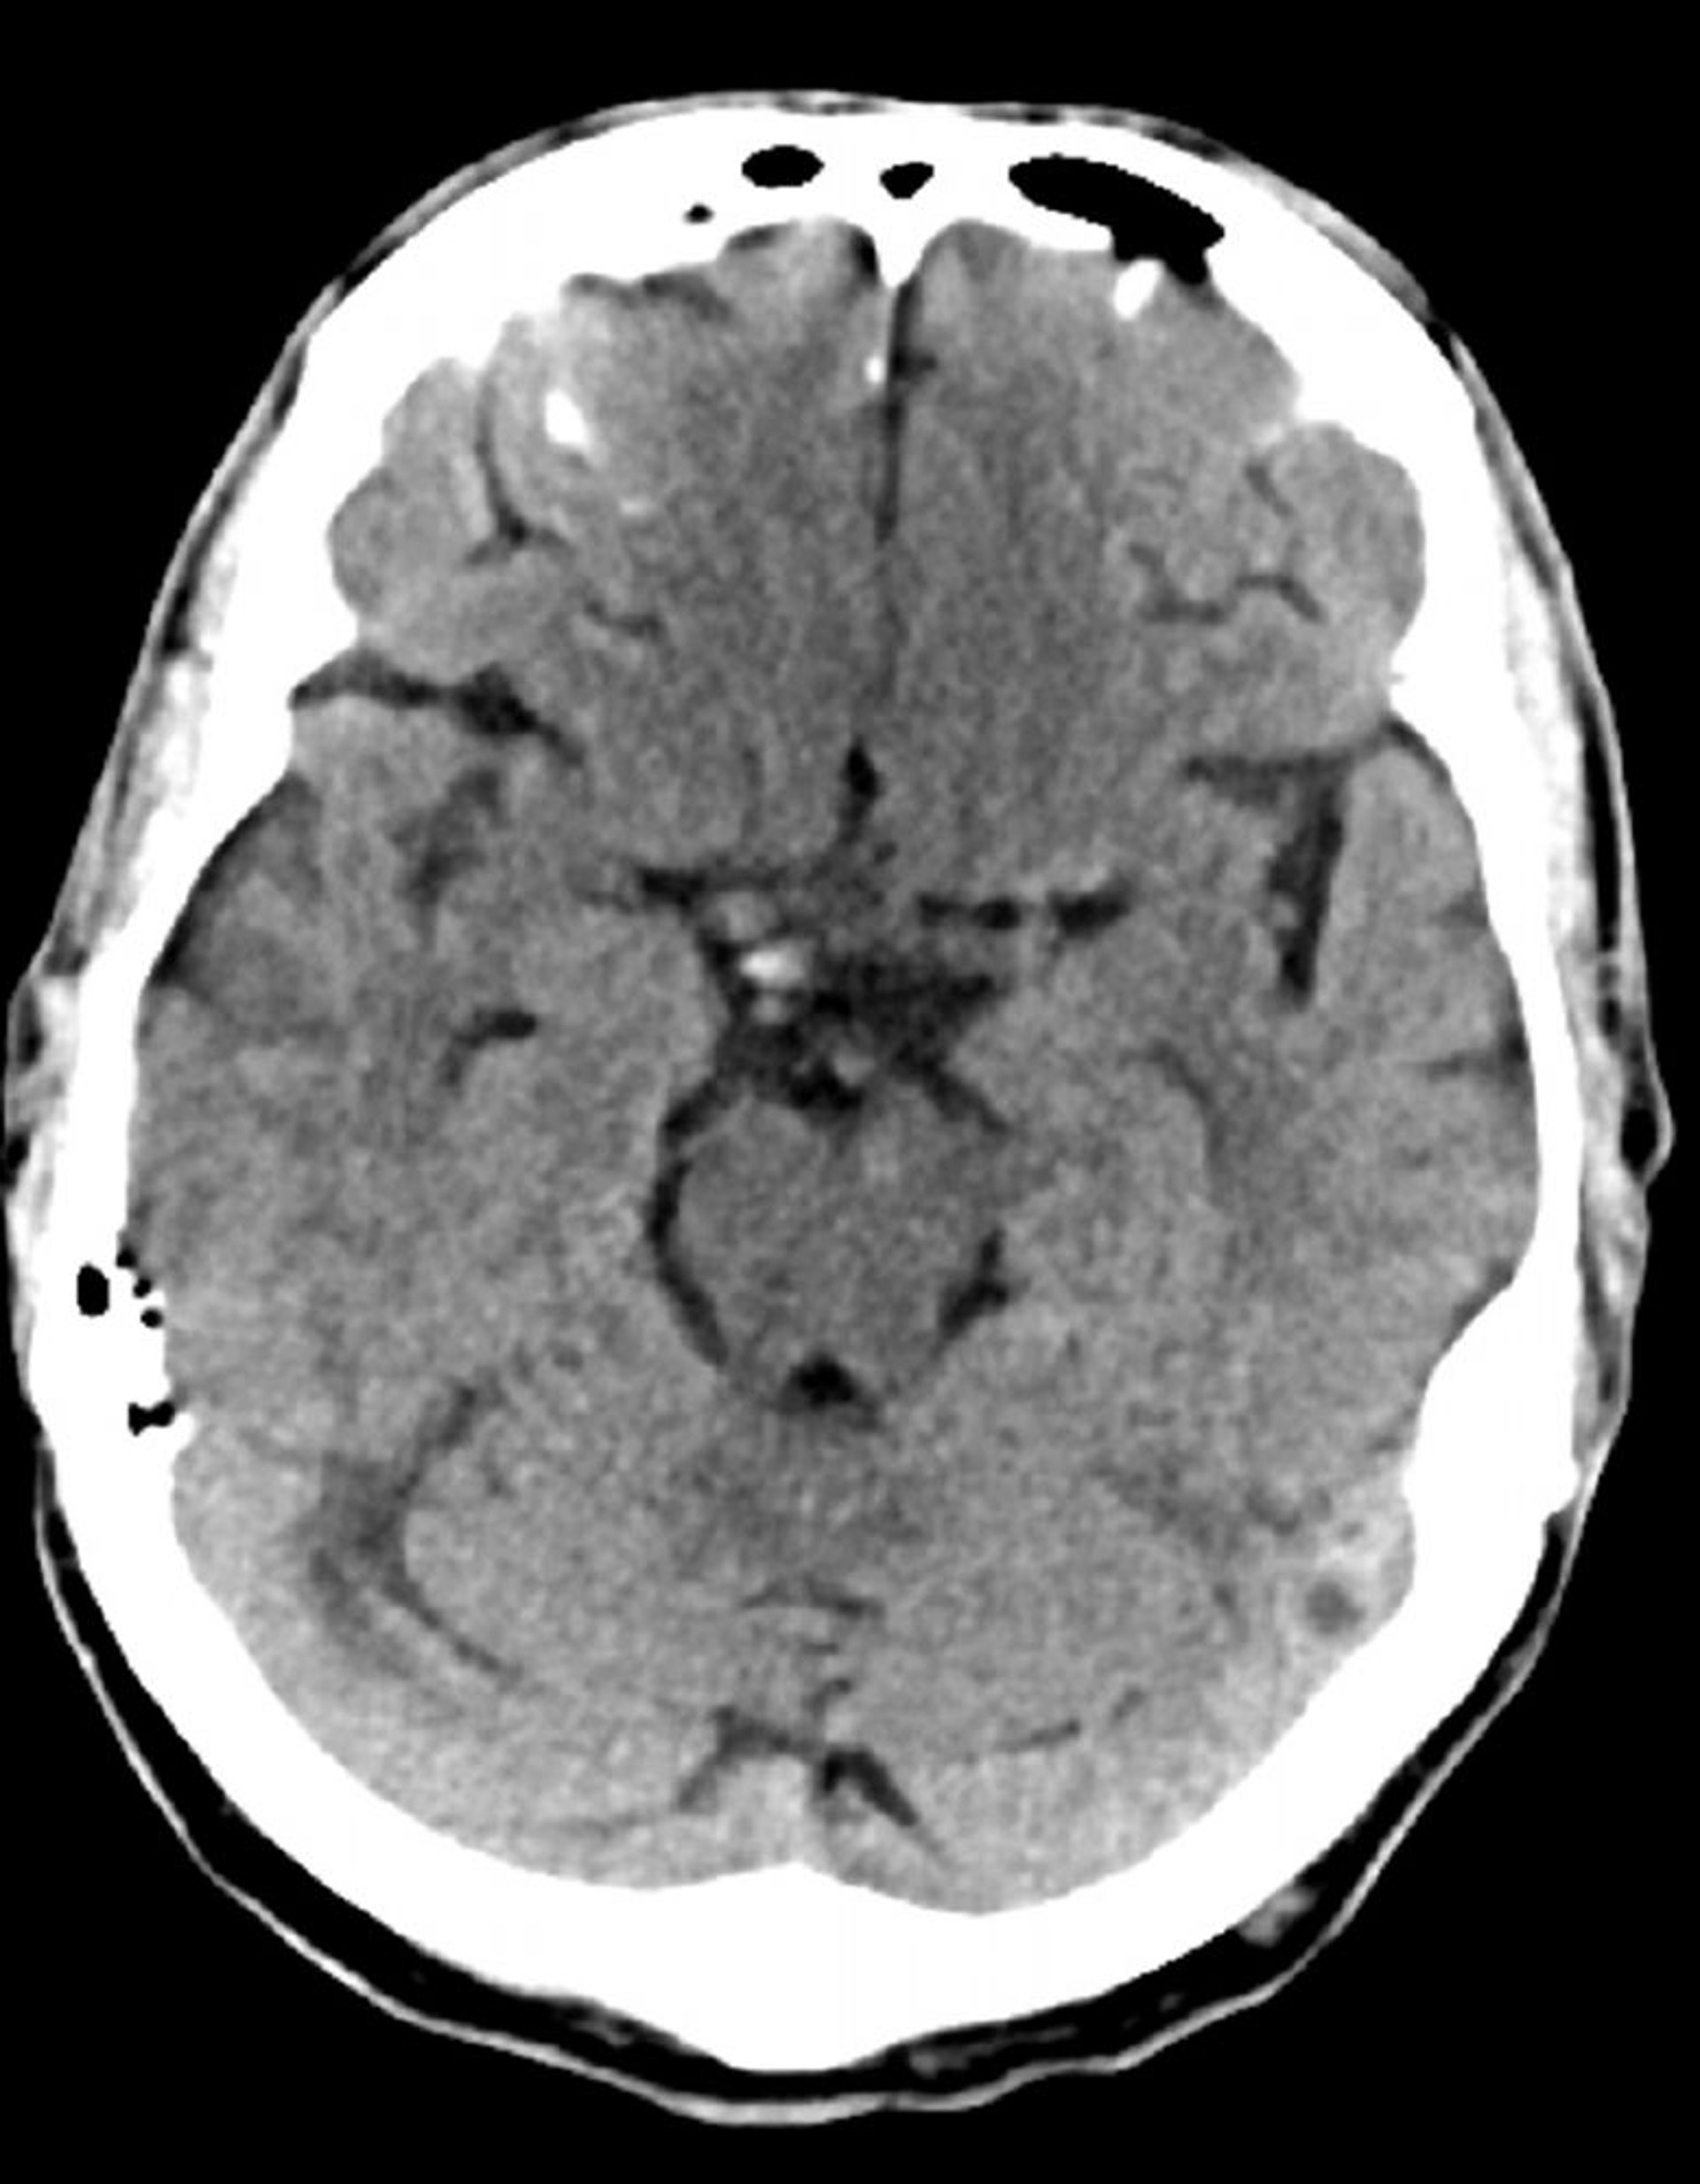

Стандартное КТ-сканирование головы (взрослые, возраст 74 года) – слайд 7

Это изображение –обычная компьютерная томография головы взрослого человека в возрасте 74 лет. По сравнению со стандартной компьютерной томографией головы пациента 30-летнего возраста, на данном изображении желудочки и мозговые борозды больше. Эти показатели являются нормальными для данной возрастной группы.